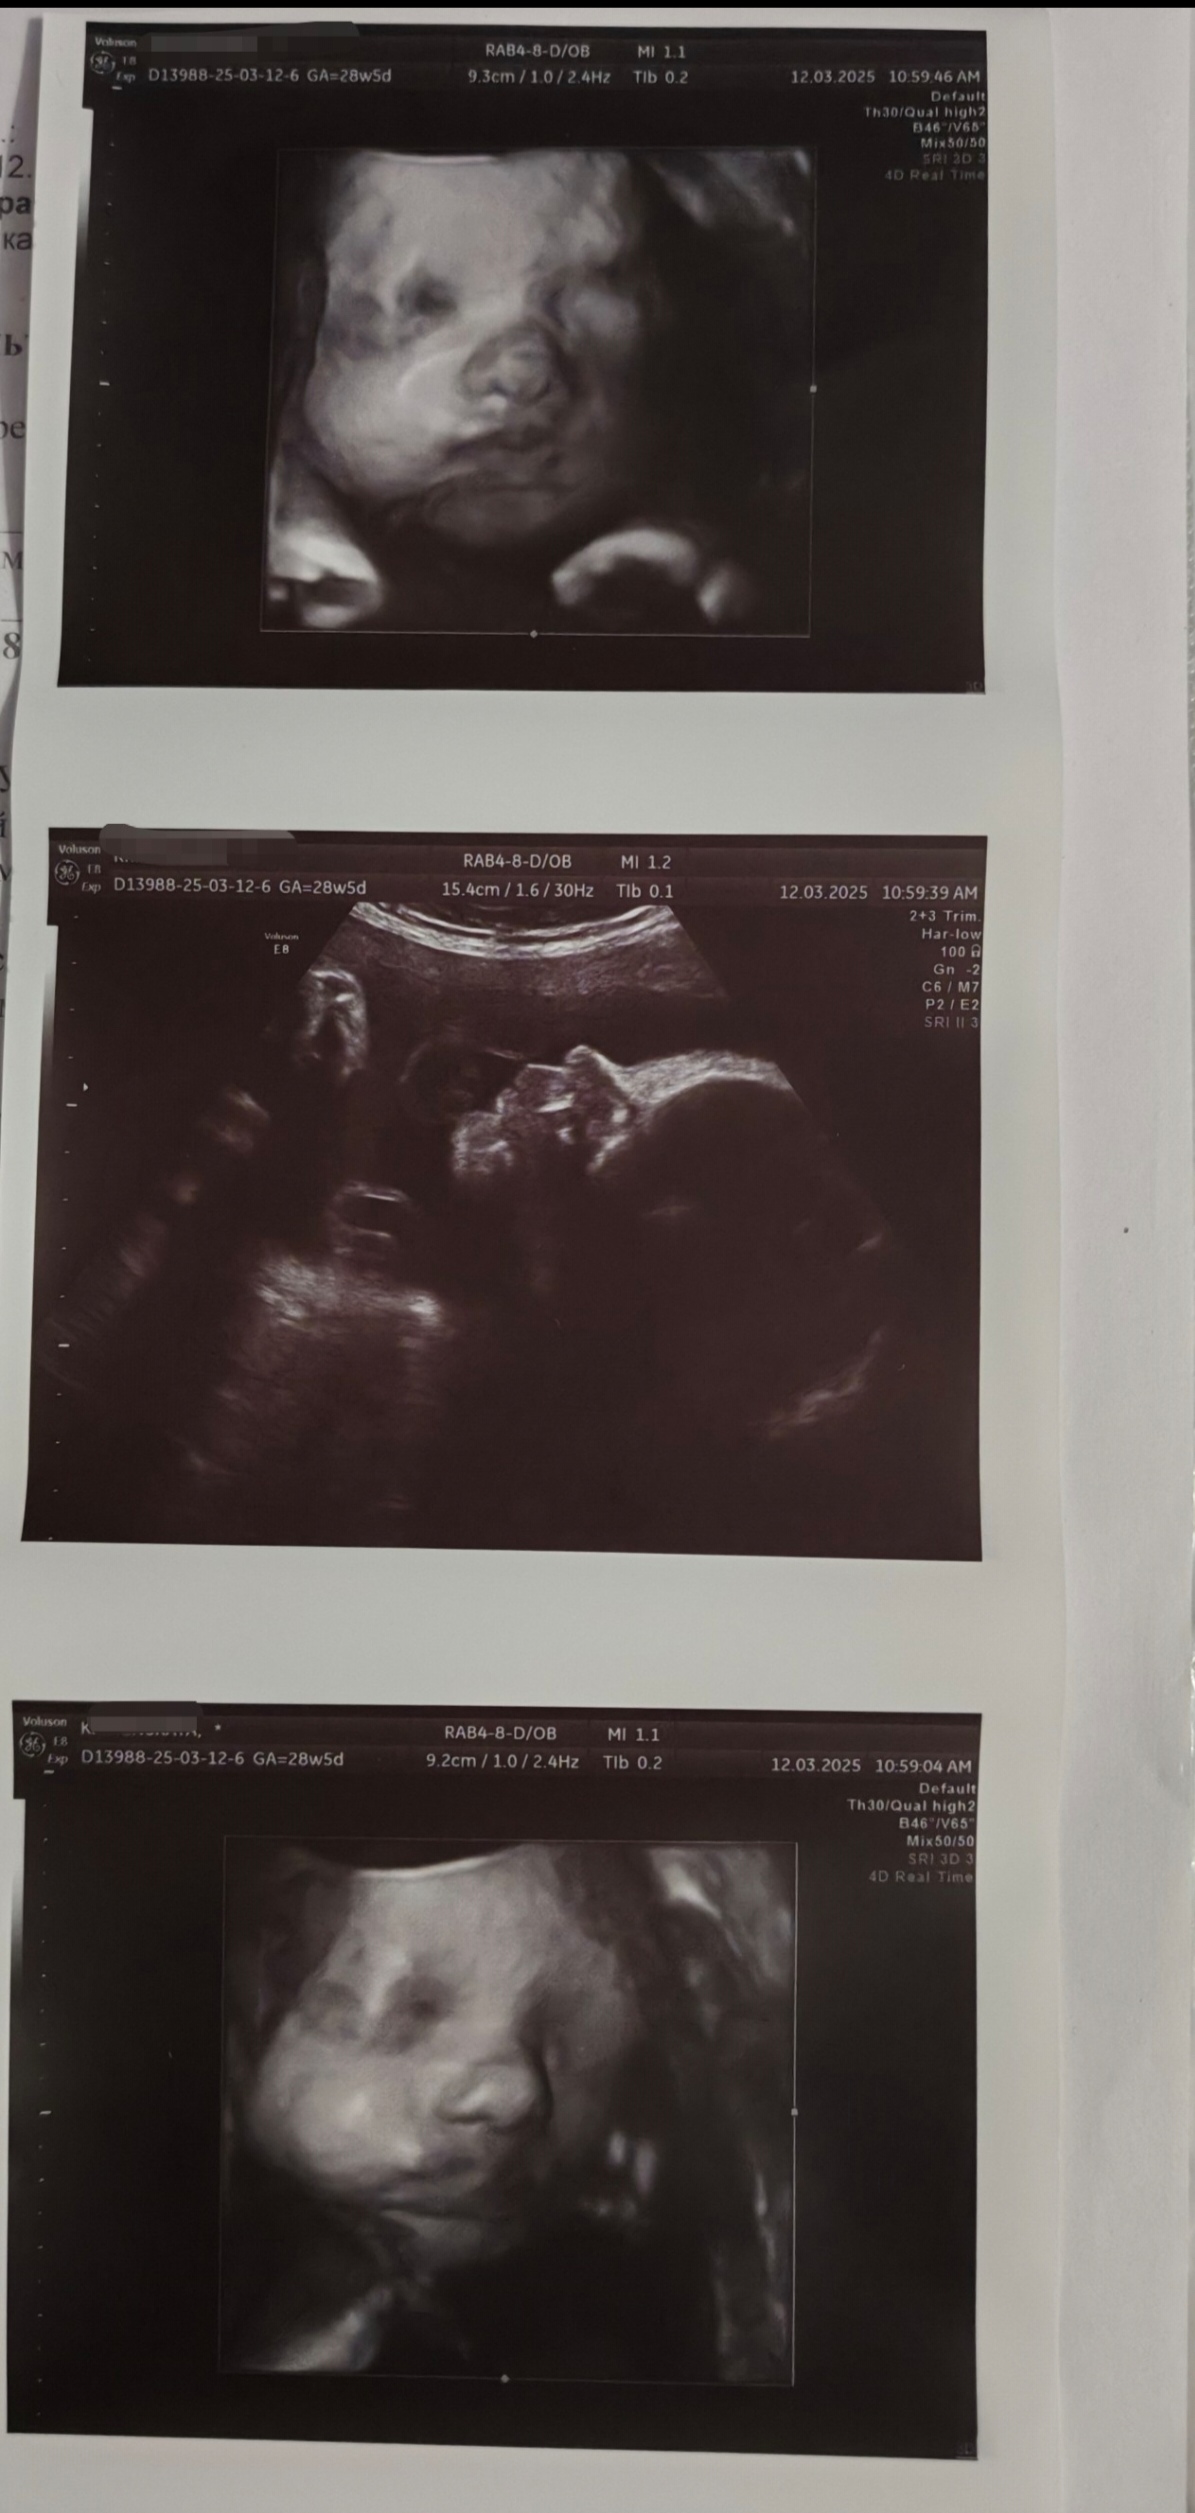

Ещё одно узи, на этот раз 3д :)

Радиомама, щёки да, хомяк такой 😅 сравнила с первой дочкой, даже что-то общее есть 😆 (первая доча слева, срок примерно одинаковый) ой, я узи обожаю делать 😆 хлебом не корми, дай на узи сбегать) я у этого врача и с первой дочкой узи делала и со второй, но вот с января к ней вообще что-то попасть невозможно было 😑 пришлось несколько узи делать в других местах, не то пальто, конечно. А тут она и меня знает и все рассказывает, показывает, разрешает на телефон видео снимать, а когда 3д включила, у меня вообще сегодня поросячий восторг был 😆 Изображение

Радиомама, Первая да, родилась 3260гр) да и эта, думаю, примерно такая же будет, там ещё мне кажется в воде всё раскисает у них 😆😆😆